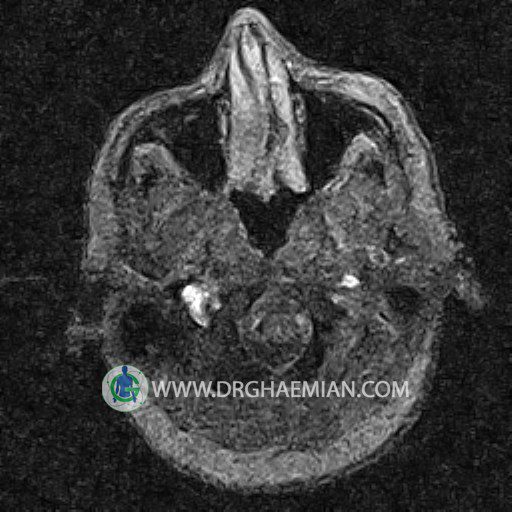

ام آر وی یک روش تصویربرداری دقیق و غیر تهاجمی است که برای معاینه ورید های بدن و ارزیابی سلامت رگ ها استفاده می شود. ورید ها خون را از اعضای بدن به قلب باز می گرداند تا دوباره اکسیژن و مواد مغذی به خون داده شود. ام آر وی جریان خون را ارزیابی و موارد غیرعادی مضر مانند لخته های خونی را شناسایی می کند. در این کیس ترومبوز دیواری مغز در سینوس عرضی راست و ترمبوز جزئی در سینوس عرضی چپ دیده می شود.

(With & Without contrast)

Technique: TOF ( time of flight ).

– Narrowing of left transverse sinus with filling defect & inthimal irregularity

suggestive for partial thrombosis

– Inthimal irregularity in anterior wall of right transverse sinus suggestive for mural thrombosis

are seen